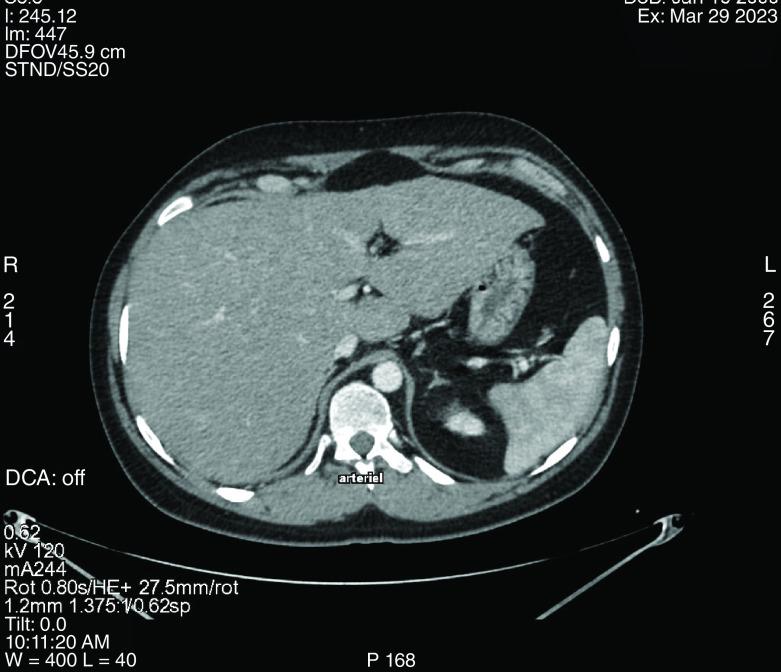

Primary hepatic lymphoma is a rare variant of non-Hodgkin's lymphoma with an incidence of 0.016% of all non-Hodgkin lymphomas. The most common histologic subtype is large diffuse B-cell lymphoma. Pathogenesis is not clearly established and undergoing immunosuppressive therapy has been proposed as a risk factor for primary hepatic lymphoma. We report an intriguing case study, featuring a 23-year-old male patient with Crohn's Disease who had been receiving a combination therapy of thiopurine and anti-TNF for 6 years and was diagnosed with primary hepatic diffuse large B-cell lymphoma.

原发性肝淋巴瘤是一种罕见的非霍奇金淋巴瘤变体,占所有非霍奇金淋巴瘤的0.016%。最常见的组织学亚型是弥漫性大B细胞淋巴瘤。其发病机制尚未明确,有人提出接受免疫抑制治疗是原发性肝淋巴瘤的一个危险因素。我们报告了一个有趣的病例研究,患者为一名23岁的克罗恩病男性,接受硫嘌呤和抗TNF联合治疗6年,被诊断为原发性肝弥漫性大B细胞淋巴瘤。